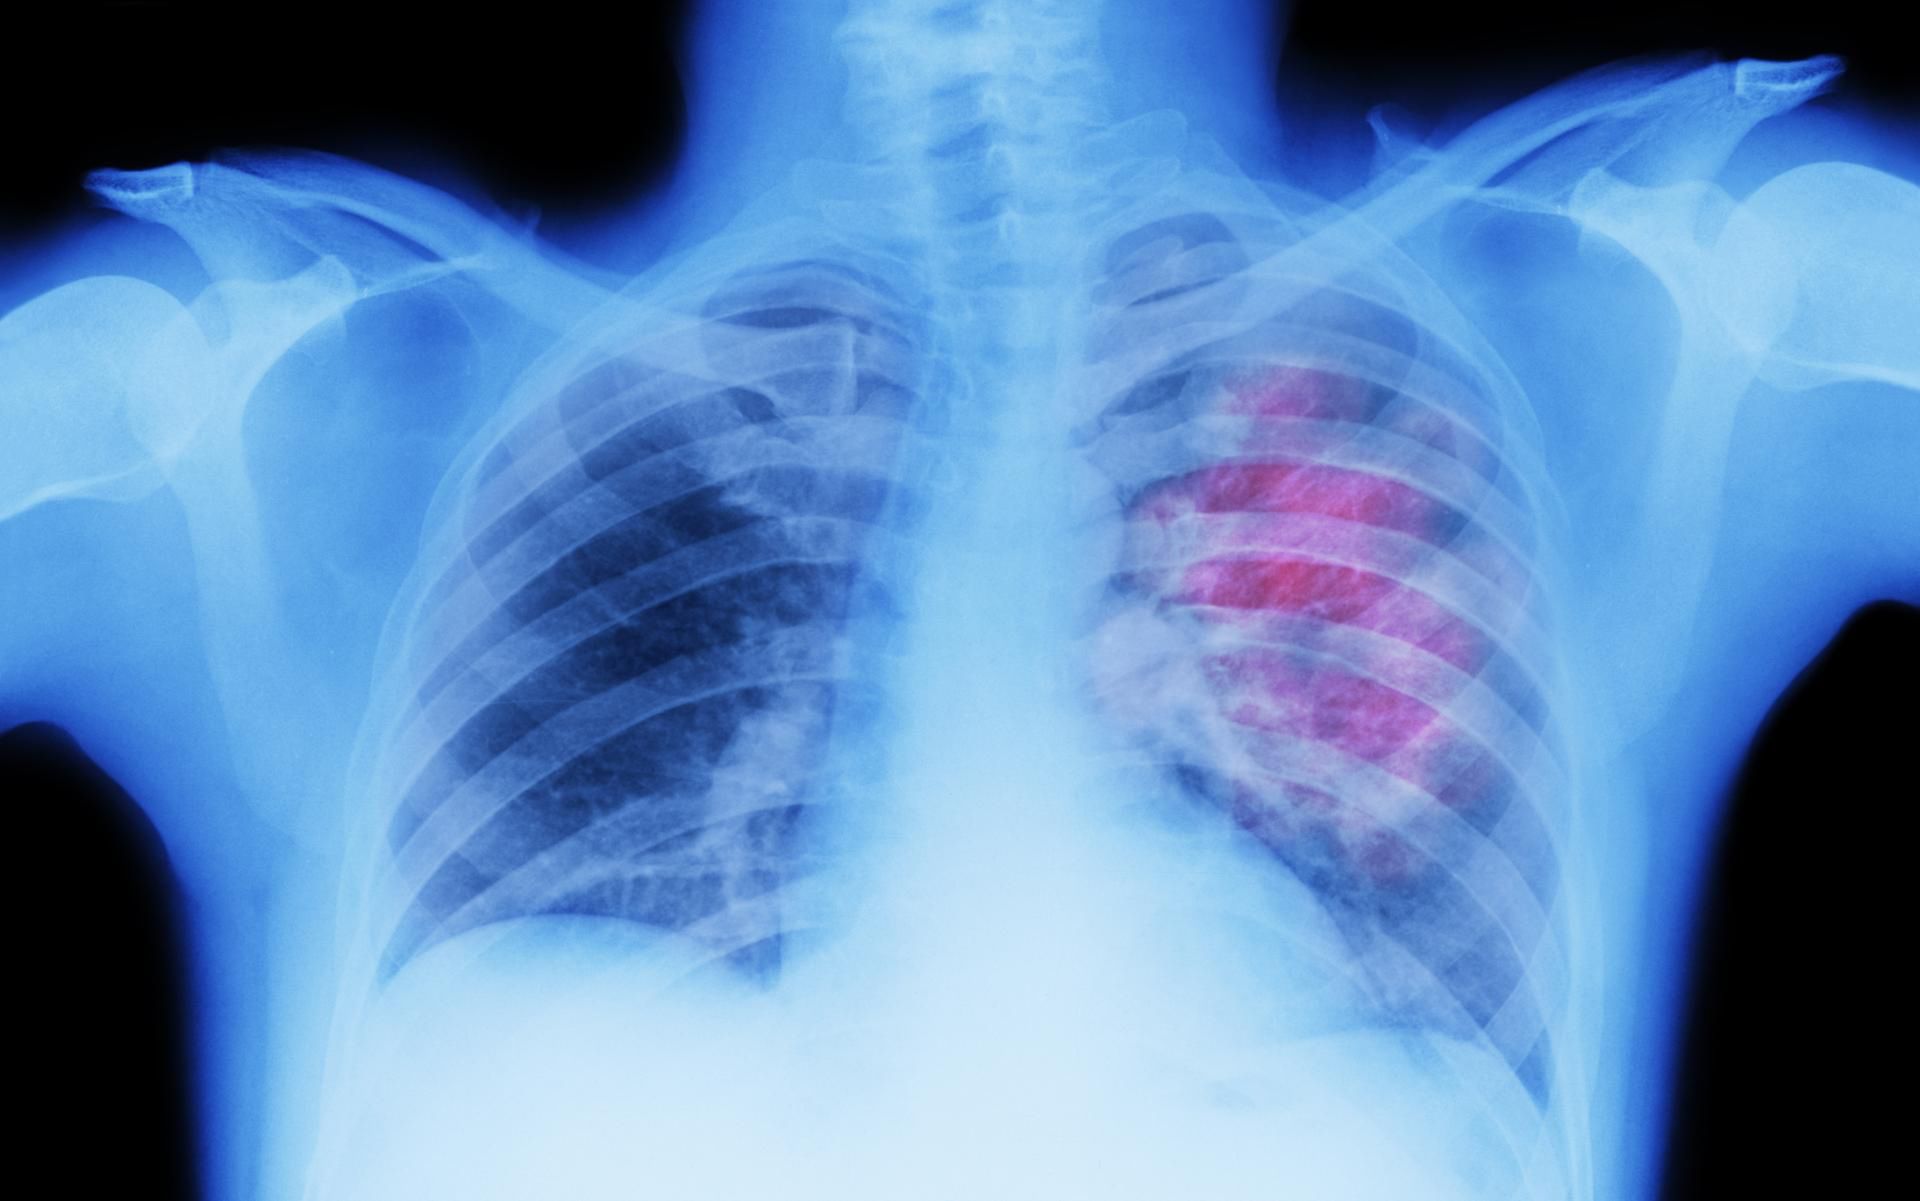

Nietypowe objawy nowotworu płuc

Nowotwór płuc głównie kojarzy się z uporczywym kaszlem, ale może powodować szereg innych objawów. Jednym z nich jest brak tchu i uczucie duszności. Objawowi temu może towarzyszyć odkrztuszanie krwi i ból barku lub klatki piersiowej.

Jeśli szybko męczysz się podczas robienia rzeczy, które zwykle nie stanowią problemu, być może czas na wizytę u lekarza. Należy pamiętać, że nowotwór płuc dotyczy nie tylko osób palących, choć to najczęstsza przyczyna.

Opuchnięte palce i paznokcie to kolejny mało znany objaw raka płuc. Zmiany w kształcie paznokci i obrzęki mogą być również oznaką rozwijającego się nowotworu. Można odnieść wrażenie, że paznokcie się unoszą i tworzą ostry kąt z naskórkiem.

Objaw polega na zwiotczeniu łożysk paznokci i pogrubieniu paliczków, nazywany jest clubbingiem lub paznokciami zegarkowymi i jest spowodowany przez przerostową osteoartropatię płuc, która powoduje stan zapalny kości i stawów.

Niektóre objawy nowotworu płuc są mało znane